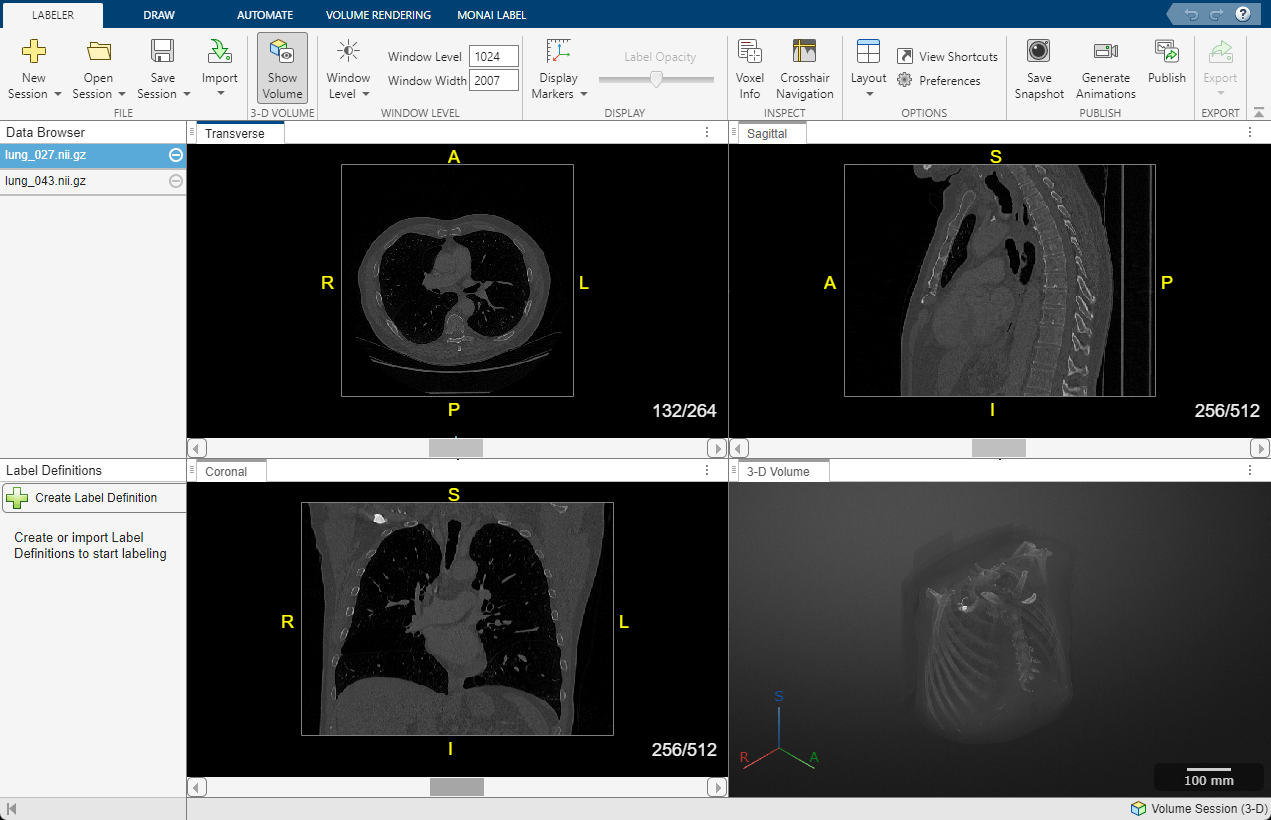

3D chest CT scan in DICOM format visualized using Medical Image Labeler in Medical Imaging Toolbox. (See documentation.)

Managing DICOM data effectively involves best practices for storage, security, and analysis. DICOM files should be stored in a structured directory system, often integrated with PACS (Picture Archiving and Communication System), to ensure efficient retrieval and long-term accessibility. MATLAB® enables you to work with medical images in DICOM and enhanced DICOM formats and directly communicate with PACS servers. It provides powerful capabilities for processing and analyzing DICOM data, including reading, writing, visualizing, and segmenting medical images.

To maintain data security and compliance, especially with HIPAA, GDPR, and other regulations, it’s essential to implement encryption, access controls, and anonymization of patient data. With the dicomanon function in MATLAB, you can remove confidential medical information from the DICOM file and create a new file with the modified values. With Image Processing Toolbox™, Deep Learning Toolbox™, and Medical Imaging Toolbox™, you can automate medical imaging workflows, extract features, and even build AI models for diagnostic support, making MATLAB a valuable platform for both clinical research and medical device development.